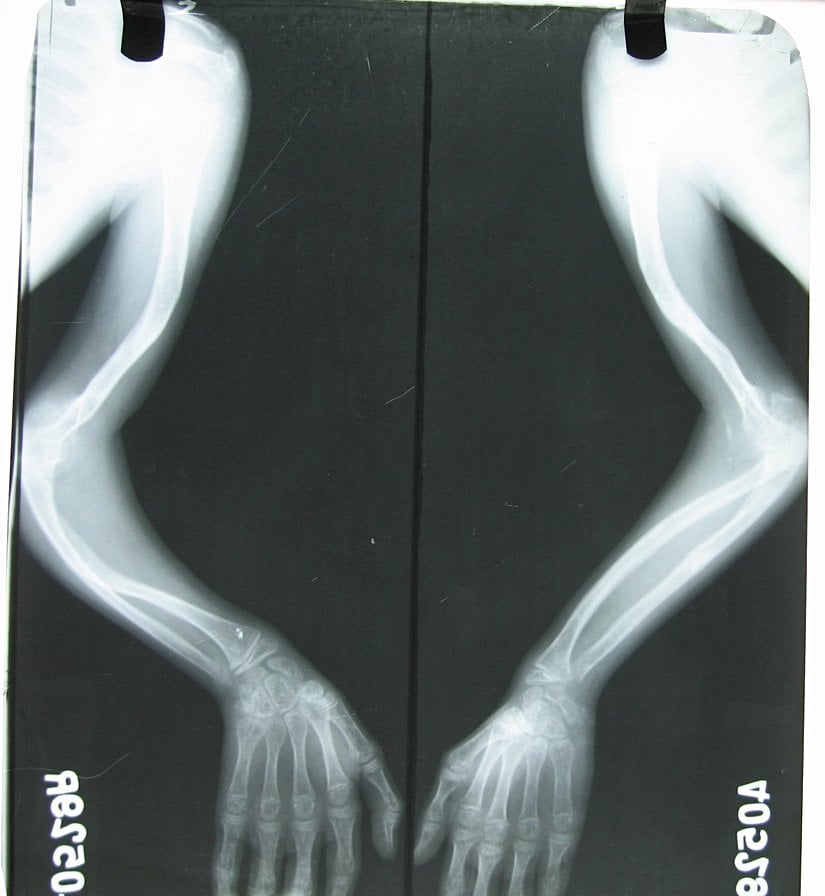

Hastalık sonucunda vücudun herhangi bir bölgesindeki ya da tümündeki kemiklerde gelişim bozuklukları ve kırılmalar meydana gelir. Örneğin kafatası kemiği, kol kemikleri, kaburgalar, bacak kemikleri, kalça kemikleri ve diğer kemiklerde sorunlar oluşur. Bu mutasyon vakaların %65'inde ebeveynlerden aktarılır, dolayısıyla gelişim sırasında kemikler vücut ağırlığı altında yeterli güçlü olamadıklarından eğilip bükülürler ve bu da vücut şekil bozukluklarına yol açar. Hastaların %35 civarında ise mutasyon "sporadik" olarak meydana gelir; yani bireyin kendi ömrü içerisinde oluşur.

Hastalık, genellikle X-ışını taraması gibi tıbbi görüntüleme teknikleri ve dışarıdan gözle görülebilir semptomlar ile teşhis edilir. Görüntüleme tekniklerinin kullanılma nedeni, vücut ekstremitleri ve omurgadaki bozulmaları teşhis etmektir. Belirtilerin Cam Kemik Hastalığı'ndan kaynaklandığı DNA analizi veya kolajen testiyle doğrulanabilir.